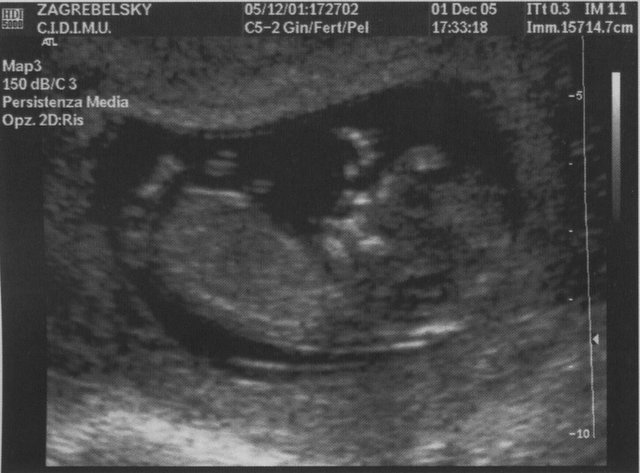

- PINETT in tutto lo splendore dei suoi 6,2 mm! (Il ...

Giornata emozionante e fortunata per una nonna, che si trova nella piacevole condizione di trovarsi, un po' per caso, con la figlia in un momento così unico. Io non ho avuto l'esperienza delle ecografie e adesso la vivo attraverso una figlia. Vantaggi infiniti dell'aver figli, o comunque di condividere la vita e le passioni dei giovani, "sostiene Pereira".Ho visto l'altra sera questo bello spettacolo teatrale tratto dal romanzo di Tabucchi dove recitava l'amico di Emanuele di Sondrio che fa l'attore ( non mi viene il nome adesso) e dove si sosteneva e mostrava appunto di come i vecchi "fanno bene" ai giovani e viceversa.